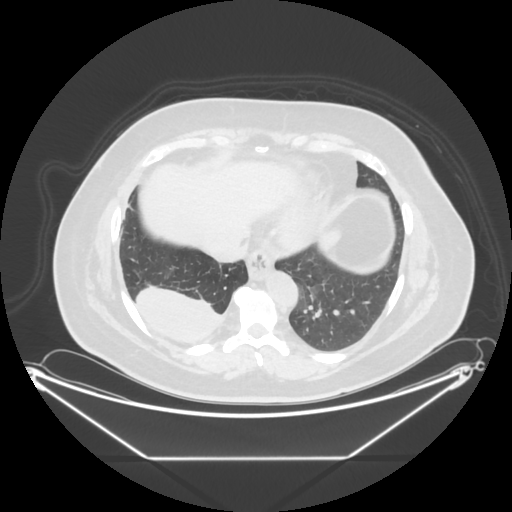

Reconstructed NATIVE CT scan (cycle consistency)

No window - Raw intensity values

Lung window (WL -600, WW 1500 β†’ Low βˆ’1350, High +150)

Mediastinum window (WL 40, WW 400 β†’ Low βˆ’160, High +240)